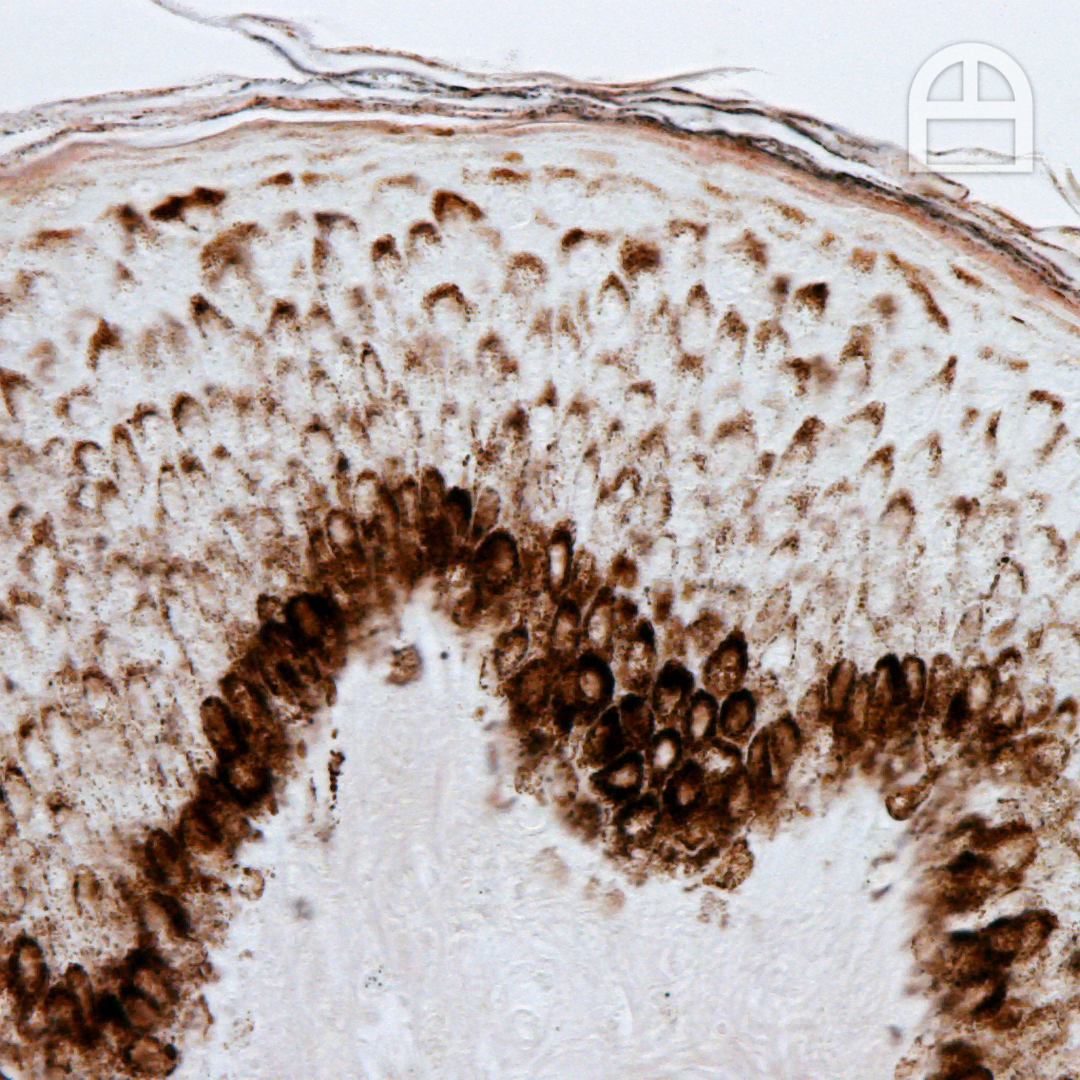

Close-up of a cross-section of biological tissue under a microscope with brown staining.